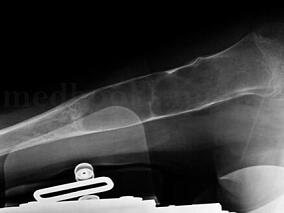

1小时条评论(1)病例介绍: 患者,14岁,主因右上臂疼痛伴功能障碍3年3个月,门诊收入院。患者于3年3个月前不慎跌倒,当即感到右肩部及右上臂疼痛,畸形并伴有功能障碍。来我院急诊就诊,摄片显示右肱骨近端溶骨破坏伴有皮质不连续,急诊考虑右肱骨骨囊肿伴病理性骨折(图1‐1...